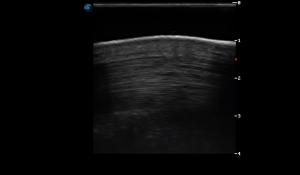

SIMON Ultrasound Database

This ultrasound database is a free resource for students and doctors!

Our collection includes videos of dogs, cats, horses, cows, humans, and many other species!